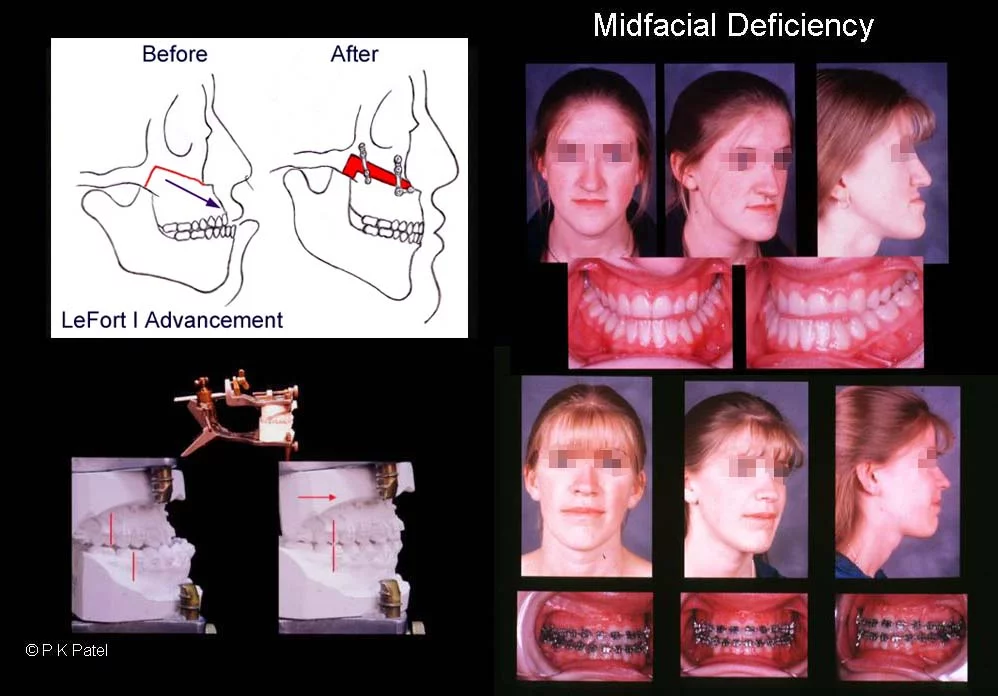

2. QUADANGULAR LEFORT + BSSO + GENIOPLASTY

quadangular lefort less risky than MLF3/LF2)

2. QUADANGULAR LEFORT + BSSO + GENIOPLASTY

quadangular lefort